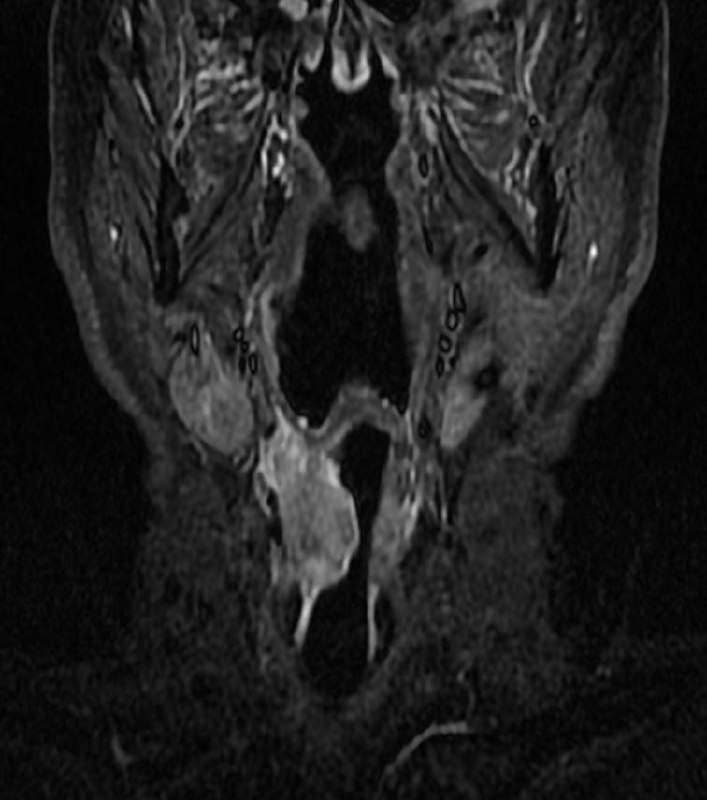

У пожилого мужчины после переохлаждения резко появилась задержка мочеиспускание, урологи утверждают, что у него – острый простатит. А на Магните – типичный рак, по крайней мере, PI-RADS 5.

Как считаете, может ли острый простатит выглядеть вот так? Асимметричный, с достаточно чётким контуром, да ещё и с быстрым накоплением контраста и быстрым же его вымыванием?

Когда рак простаты видно вот так, как здесь - исследование не вызывает отвращения, в отличие от случаев, когда приходится писать PIRADS-3..

Другое дело, что мы ж о пациентах заботимся, а не о себе, любимых, и каждый PIRADS-3 для пациента, все же, лучше, чем легко и непринуждённо обнаруживаемый, как в данном случае, PIRADS-5.

Пожелаем этому мужчине 75 лет успехов в лечении и минимума неприятных ощущений, которыми, неизбежно, такое лечение сопровождается.